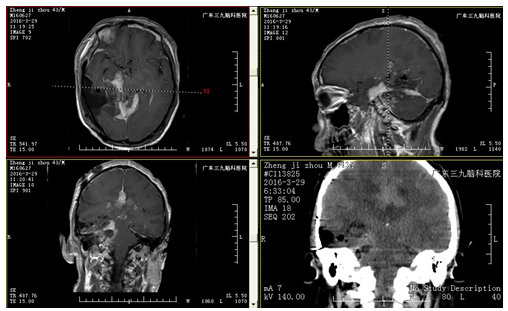

入院后完善相关检查,复查头颅MRI示:1.右侧中后颅窝及大脑镰后部脑外及部分脑内占位病变,累及桥前池及右侧内听道、右侧海绵窦区,考虑肿瘤性病变,全脑血管造影示:右侧中后颅窝占位性病变异常染色,提示血供丰富,考虑窦组织细胞增生症(RDD)或不典型脑膜瘤可能;2.右侧大脑镰下疝;小脑扁桃体下疝;完善术前准备后,行全麻下中后颅窝幕上幕下占位性切除术,手术由神经外二科主任林涛主刀完成,手术顺利,术后安返病房,予营养支持、抗炎、营养神经、预防癫痫、保护胃肠道、脱水等治疗。术后复查头颅CT、MRI示:呈术后改变,肿瘤大部分切除。术后病理结果回报:不典型脑膜瘤。